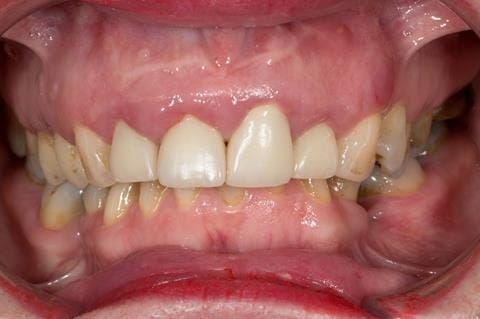

- High smile line showing gum above gingival zeniths of upper front teeth when smiling. Aesthetic failure of the upper four incisors with inflammation of the gingivae and mis-match of the gingival zenith levels.

- Other than the maxillary incisors the remaining dentition was in marginally better condition being moderately to heavily restored. Many will probably require replacement and restoration from time to time mainly from wear and tear owing to occlusal forces.

Following consultation and second discussion appointment the patient chose to have option 3 namely, a maxillary cobalt chromium based partial denture/protective occlusal splint. The clinical situation and treatment process is shown in detail below with photographs. The patient was successfully rehabilitated with this and her quality of life considerably improved. The clinical work was provided by Finlay and the technical work by Rowan.